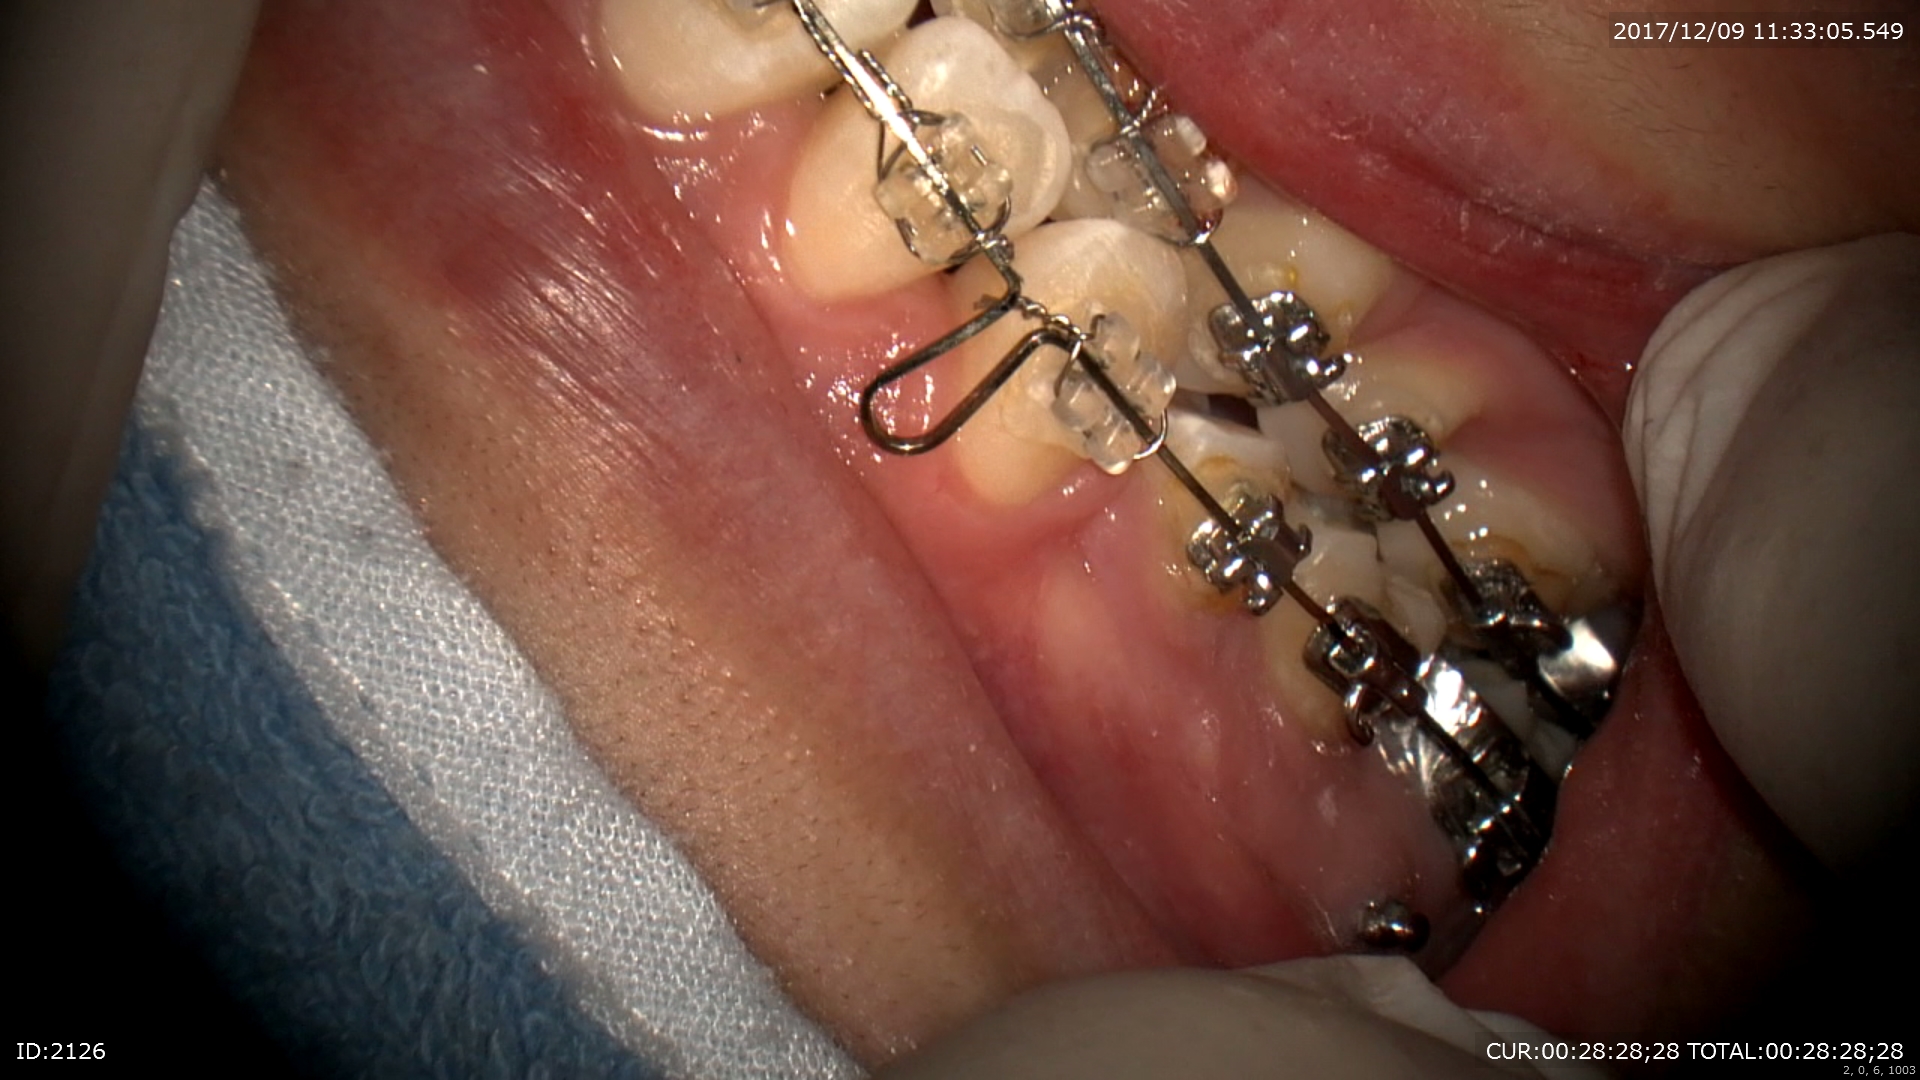

次のケースも幸せ。矯正。下あごの位置を修正する矯正治療終盤戦。大分咬んできました。

スペース

クローズの為のシンチバック

綺麗なお顔、かみ合わせができました。嬉しかった!